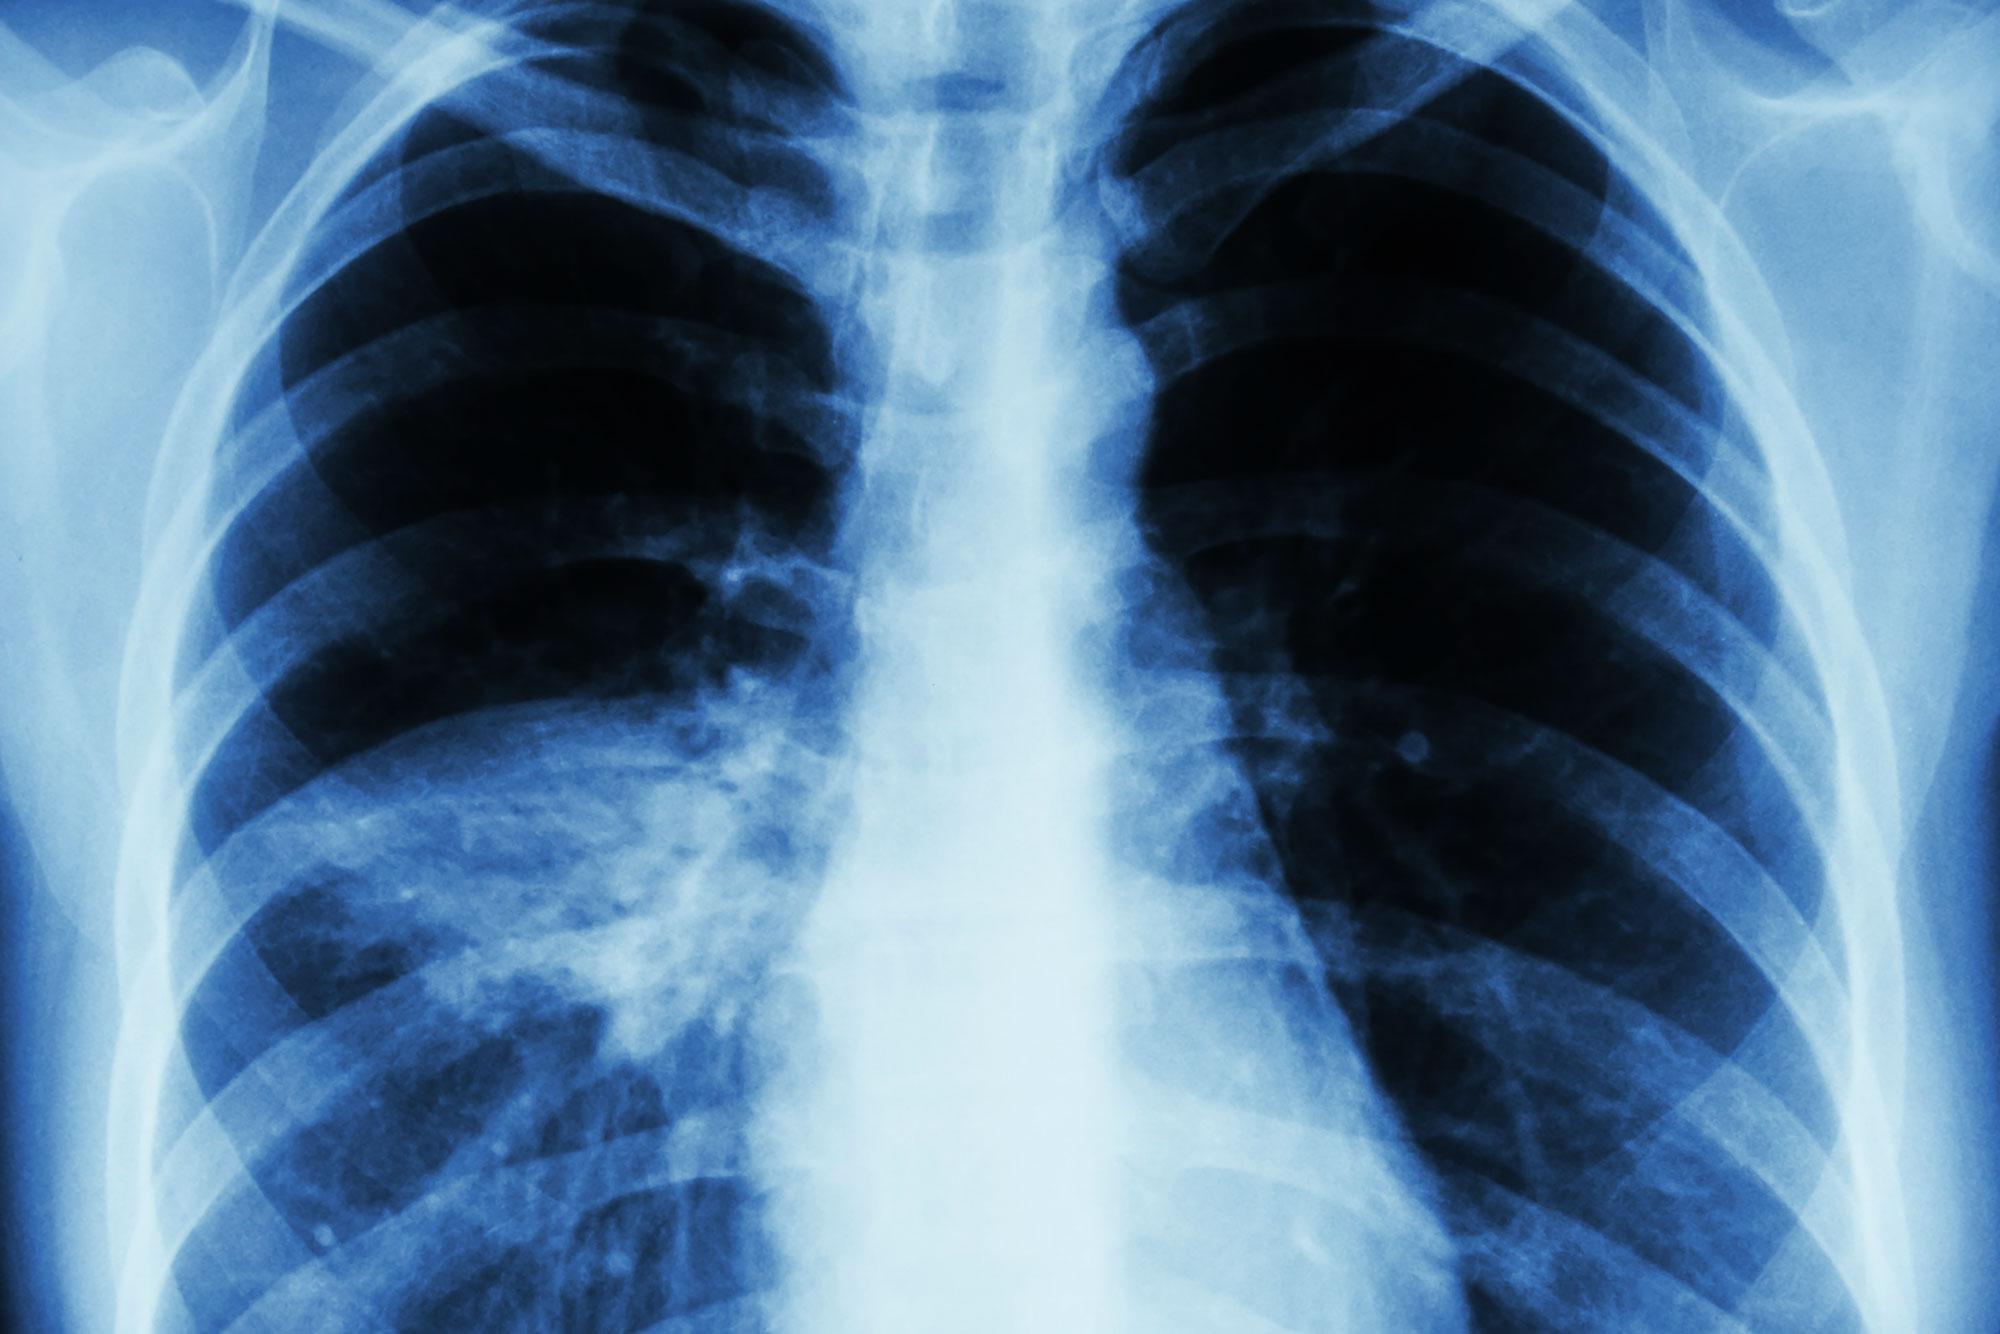

Компьютерная томография (КТ) легких считается «золотым стандартом» диагностики воспаления легких, в частности пневмонии, ассоциированной с COVID-19. На томограммах — множественных сканах дыхательного органа в трех плоскостях — визуализируются нефункциональные участки уплотнения или инфильтрации легочной ткани.

В этой связи очень важно вовремя распознать пневмонию и начать лечение. КТ легких — единственный метод диагностики, который позволяет выявить очаги инфильтрации и оценить степень их выраженности, даже если поражено менее 5% легких.

1) Наличие «матовых стекол» на сканах КТ, их локализация, консолидация. «Матовые стекла» — это светлые участки легких на томограммах, которые свидетельствуют об очагах инфильтрации. Плотная ткань не пропускает рентгеновские лучи. «Матовые стекла» — основной признак поражения легких на КТ. Их распространенность и консолидация соответствует тяжелым стадиям пневмонии КТ3 и КТ4.

2) Утолщение междолькового пространства легких или «симптом булыжной мостовой» — ткань легких на сканах КТ имеет внешнее визуальное сходство с брусчаткой. Соответствует тяжелой стадии пневмонии КТ4.

3) Симптом «обратного гало» или «ободка́» — на томограммах выглядит как светлые кольца. Это участки уплотнения вокруг очага инфекции. Считается признаком организующейся пневмонии.

4) Ретикулярные изменения — тонкие линии патологически измененного легочного интерстиция, формирующие сеть.![]()

На сканах КТ легких обнаружены «матовые стекла» — менее трех. Диаметр очага инфильтрации не превышает 3 см, иные патологические изменения легких не обнаружены. У пациента может быть высокая температура, затрудненное дыхание, кашель, иногда явные симптомы отсутствуют. Лечиться от внебольничной пневмонии КТ1 можно в амбулаторных условиях и дома после консультации врача.

КТ2 означает, что обнаружено более трех участков воспаления легких по типу «матового стекла» диаметром не более 5 см. Также как и в случае с КТ1, это внебольничная пневмония, при которой не нужна госпитализация. Пациент лечится дома, соблюдая рекомендации врача. КТ легких поможет ответить на вопрос — имеется ли активный воспалительный процесс и тенденция к консолидации «матовых стекол».

Обнаружены множественные участки «матового стекла» с тенденцией к консолидации. Это основной признак, но возможны и другие: ретикулярные изменения, «дерево в почках» или центрилобулярные очаги. При пневмонии КТ3 поражено более 50% легких, нужна срочная госпитализация и интенсивная терапия. Множественные инфекционные очаги и подавленные защитные силы организма способствуют тому, что переход от КТ3 к КТ4 происходит быстрее и легче, чем от КТ1 к КТ2.

Критическая стадия поражения легких, когда более 75% легких не участвует в газообмене. На томограммах визуализируется как диффузное поражение лёгочной ткани с ретикулярными изменениями и симптомом «булыжной мостовой», гидроторакс.